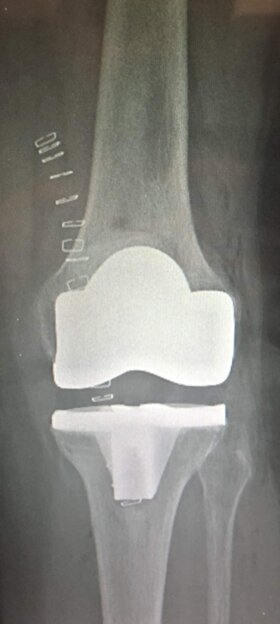

A sinistra radiografie pre-operatorie che evidenziano una grave gonartrosi diffusa con presenza di osteofiti periarticolari e deformità associata (ginocchio varo).

A destra radiografia post-operatoria in AP di intervento chirurgico di Artroprotesi di ginocchio cementata, unico trattamento possibile con pz che presentava dolore continuo e zoppia. Ho utilizzato una protesi con risparmio del legamento crociato posteriore (CR) chiamata Persona  in quanto molto anatomica, cioè rispettante l’anatomia del ginocchio del pz.